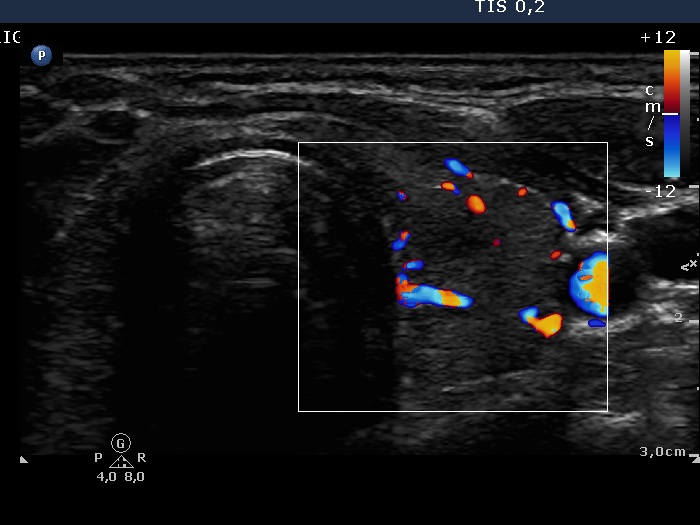

Second examination 9 months later (2nd row of images)

Clinical data: The patient had no complaints except for a 6 kg weight in gain.

Palpation: unchanged.

Results of blood tests: euthyroidism on daily 10 mg methimazole (TSH 3.58 mIU/L, FT4 12.7 pM/L).

Ultrasonography: Compared with the first examination, the thyroid has decreased in size and the echo structure became less hypoechogenic. The vascularization remained unchanged.

Suggestion: daily 5 mg methimazole.